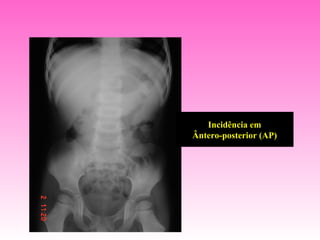

Incidência em

Ântero-posterior (AP)